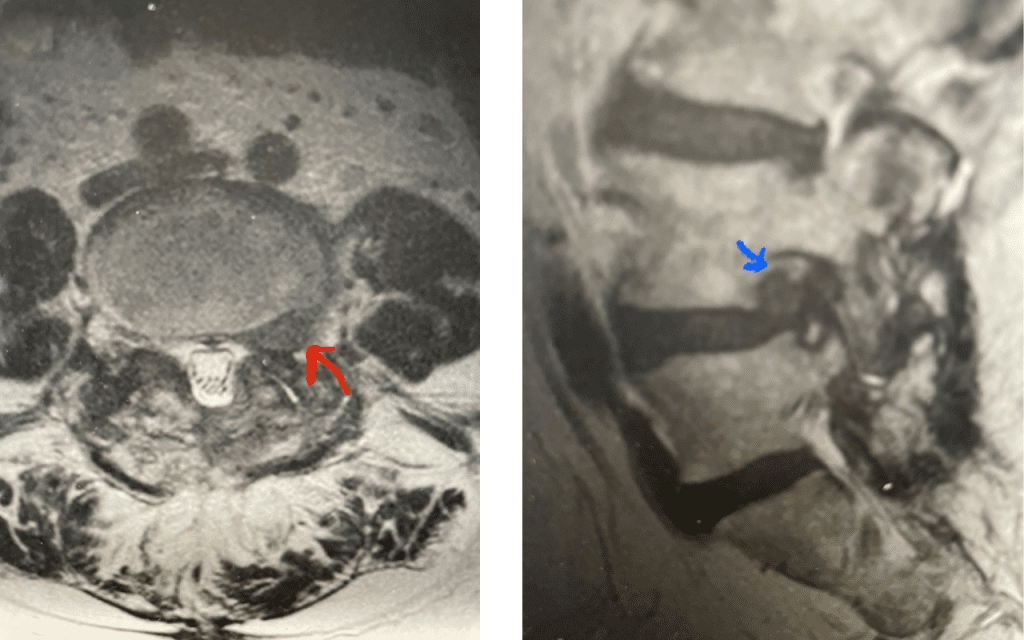

Fig 6: Axial T2-weighted lumbar MRI revealing a large extraforaminal disc herniation with severe compression of the left L3 nerve (red arrow).

Fig 7: Sagittal T2-weighted lumbar MRI with side by side comparison of the normal open right L3-4 foramen (red arrow) compared to the left L3-4 foramen filled with a large disc fragment (red arrow).

Here is a case of an extraforaminal disc fragment causing severe pain and weakness: This 60-year-old male presented with severe anterior thigh pain, numbness, and weakness for 3 weeks. He had failed epidural steroid injections. His left leg buckled when he walked. Imaging revealed a massive left L3-4 extraforaminal disc herniation, beyond the facet (Fig 6). This was severely compressing the left L3 nerve root in the L3-4 foramen (Fig 7). It was felt that the patient required surgery, as he would not be able to participate in physical therapy and had a neurological deficit. We performed an extraforaminal approach and removed a massive disc fragment that was revealed as the intertransverse membrane was reflected from the L4 transverse process-facet junction. We were able to visualize the L3 spinal root exiting above that had been compressed by the large fragment we removed (Fig 8). The patient post-op had a dramatic improvement neurologically and with significantly improved pain in his leg.